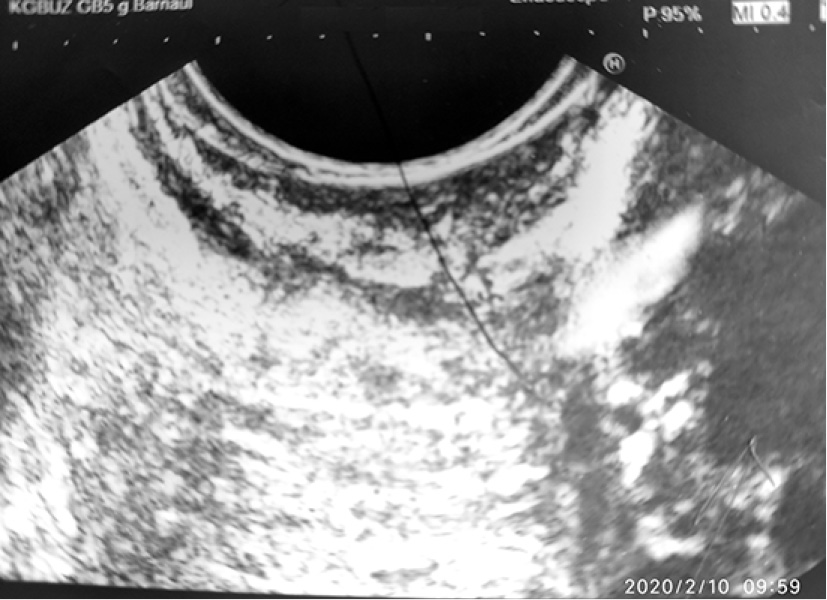

С диагнозом: «Tumor брюшной полости» поступил 02.07.2019 г. в хирургическое отделение КГБУЗ «Городская больница № 5 г. Барнаула», где провели уточняющую диагностику – эндоультрасонография от 03.07.2019 г. Видеогастроскоп проведён в желудок. Стенки желудка хорошо расправляются воздухом. В просвете желудка на большой кривизне дистальной части тела желудка на 2/3 шаровидное эластичное выбухание с подвижной гиперемированной слизистой оболочкой диаметром до 70 мм (рис. 5–7), эндосонограф свободно проведён. Сканирование в режиме 7,5–10,0 МГц. Полостное жидкостное образование диаметром 63 мм, пристеночно содержит гипоэхогенную ткань толщиной местами до 15 мм. Капсула гиперэхогенная до 1,4 мм. ЦДК (-). Образование расположено в подслизистом слое. Чётко прослеживается мышечный слой за её пределами (рис. 8, 9). Между желудком и печенью гипоэхогенная ткань с наличием сосудов и анэхогенной полостью до 10 мм (рис. 10).

Рис. 8. Образование расположено в подслизистом слое. Чётко прослеживается мышечный слой за её пределами

Рис. 9. Образование расположено в подслизистом слое. Чётко прослеживается мышечный слой за её пределами